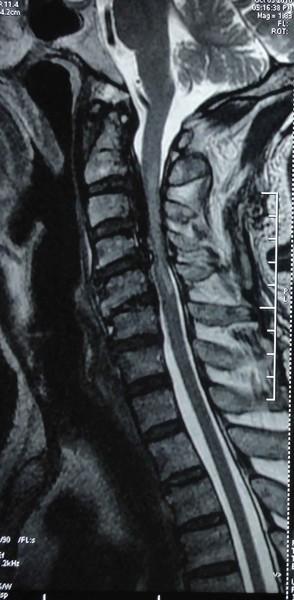

颈椎病核磁共振图解

颈椎病核磁共振图解,颈椎核磁片图解教程

颈椎病专题(三):带你了解外伤后的颈脊髓损伤

颈椎核磁片图解教程

颈椎核磁共振图片图解

颈椎核磁共振

核磁共振图解

核磁共振图片

核磁共振片子

颈椎病片子

严重颈椎病图片

颈椎病图片症状